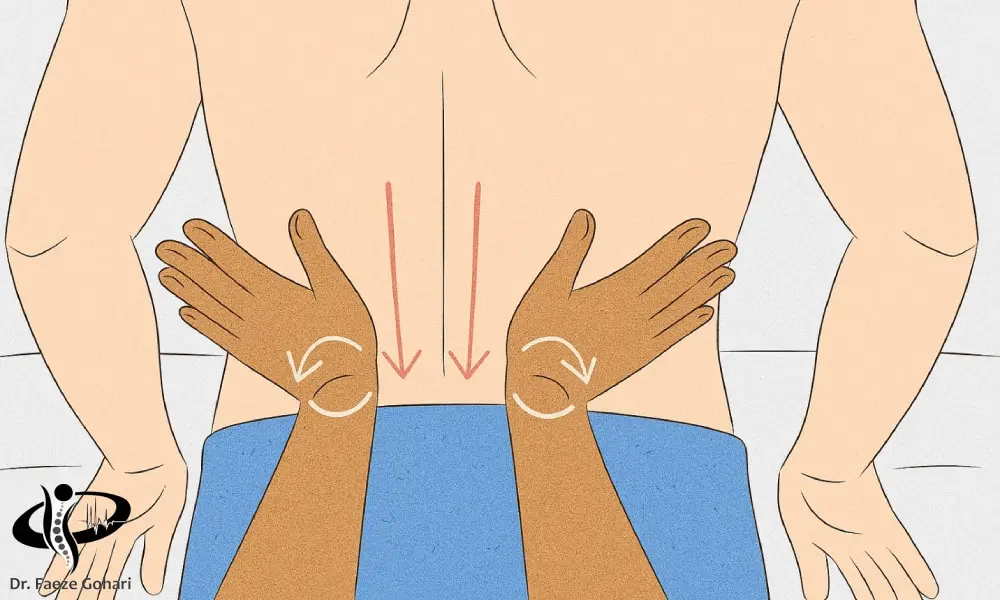

ماساژ

ماساژ یکی از روشهای مؤثر و کمخطر برای کاهش دردهای عضلانی کمر است که با بهبود گردش خون، شلکردن عضلات منقبض و کاهش تنشهای عضلانی عمل میکند. در مواردی که کمردرد ناشی از اسپاسم یا خستگی عضلات باشد، ماساژ میتواند باعث تسکین فوری و تسریع روند ترمیم عضله شود. علاوه بر اثرات فیزیکی، ماساژ با کاهش استرس و افزایش احساس آرامش روانی نیز به تسکین درد کمک میکند (منبع).

چه نوع ماساژی مناسب است و چگونه انجام شود.

- ماساژ ملایم و سطحی با حرکات دایرهای، فشاری یا مالشی در ناحیهی دردناک توصیه میشود.

- از روغنهای گیاهی با خاصیت ضد التهاب مانند روغن نعناع، زنجبیل یا اسطوخودوس استفاده کنید.

- فشار دست باید یکنواخت و ملایم باشد، از وارد آوردن فشار زیاد یا حرکات سریع و خشن خودداری شود.

- مدت زمان مناسب برای ماساژ ناحیه کمر حدود ۱۰ تا ۱۵ دقیقه در هر نوبت است.

- ماساژ را میتوان یک تا دو بار در روز، بسته به شدت درد، تکرار کرد.